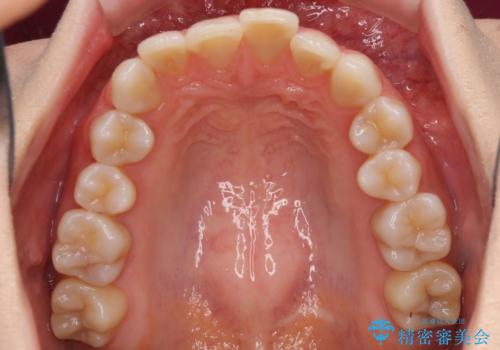

前歯の突出感とデコボコをインビザライン矯正で改善

- 上下前歯の突出感とデコボコを気にして来院された患者様です。

インビザラインによる上下歯列の側方拡大と後方移動、IPR(歯と歯の間を削る)にるスペースの獲得により歯列を整えることとしました。

骨格的な左右差があったため、上下の正中を合わせることができませんでした。

骨格の差は改善できないため、奥歯の咬み合わせに物足りなさを感じましたが、奥歯の咬み合わせによる不自由はなく、口元の突出感も改善することができました。